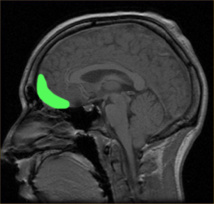

"En una situación social difícil, la corteza orbitofrontal de un individuo sano se activa, con el fin de inhibir los impulsos agresivos y de mantener una interacción normal", explica Sandi. "Pero en las ratas que estudiamos, nos dimos cuenta de que había muy poca activación de la corteza orbitofrontal. Esto, a su vez, redujo su capacidad para moderar sus impulsos negativos. Además, esta reducción de la activación vino acompañada por la sobreactivación de la amígdala, una región del cerebro que está implicada en las reacciones emocionales”.

"Otros investigadores especializados en el estudio del cerebro de los humanos violentos ya habían observado el mismo déficit en la activación orbitofrontal, así como la misma y simultánea inhibición reducida de los impulsos agresivos. Es asombroso; no esperábamos encontrar estos niveles de similitud", afirma Sandi.